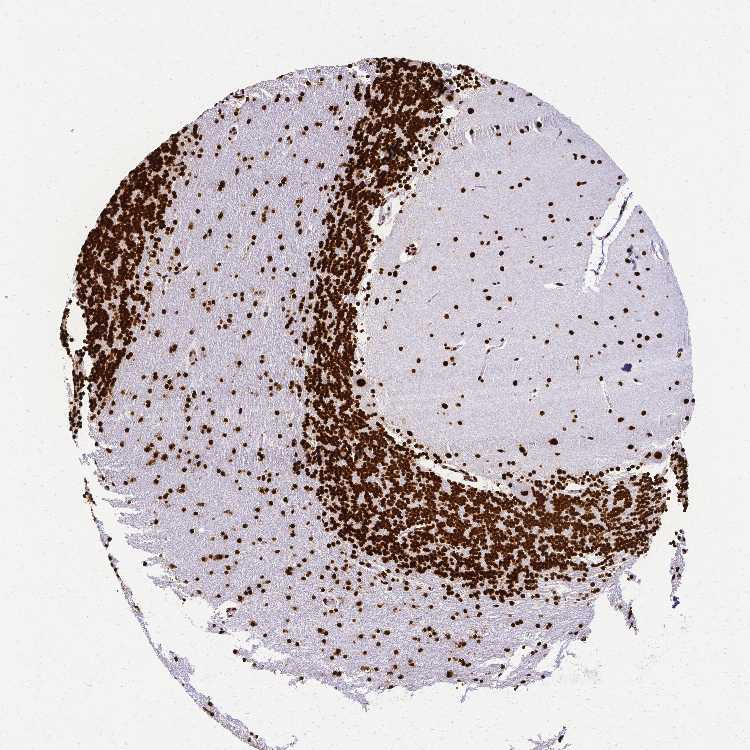

BRAIN CEREBELLUM Show tissue menu

CEREBELLUM - Expression summary

CEREBELLUM - Antibody stainingi

Antibody staining in the annotated cell types in the current human tissue is reported as not detected, low, medium, or high, based on conventional immunohistochemistry profiling in selected tissues. This score is based on the combination of the staining intensity and fraction of stained cells.

Each image is clickable and will lead to virtual microscopy that enables deeper exploration of all samples and also displays staining intensity scores, fraction scores and subcellular localization as well as patient and tissue information for each sample.

Antibody HPA047513Antibody HPA054689Antibody CAB009886

Purkinje cells HighHighMedium

Cells in granular layer HighHighLow

Cells in molecular layer HighHighLow